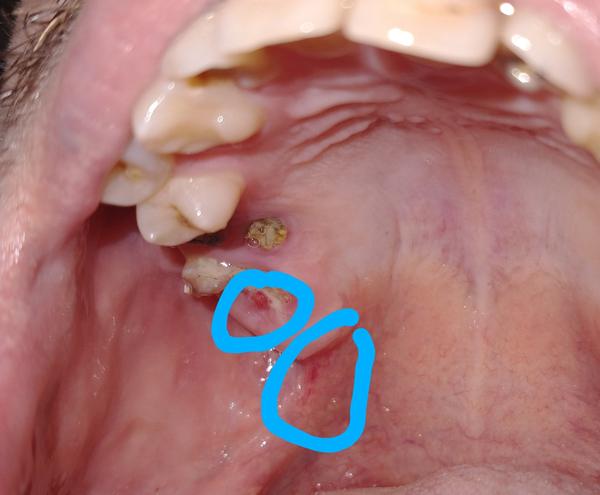

pred pár dňami som si všimol, že mám červený fľak na ďasne pri pokazenom zube, z ktorého sa mi odlomilo asi pred 1-2 mesiacmi. Keď si umývam zuby, tak pri dotyku kefkou to zabolí a trocha krváca, ale inak to nebolí a ďasno mám tvrdé. Mám 22 rokov, som nefajčiar a alkohol tiež nepijem.

Môže ísť o niečo vážne?

najskôr pôjde o podráždenú sliznicu, neznamená to hneď nejaké vážne ochorenie.

Preplachujte si ústnu dutinu Corsodylom. Ak by sa stav nezlepšoval, tak je potrebné nález ukázať Vášmu lekárovi.